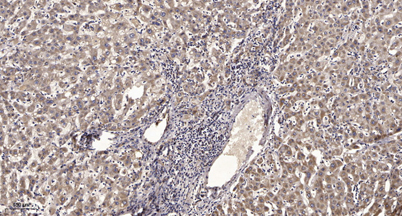

Immunohistochemical analysis of paraffin-embedded human liver cancer. 1, Antibody was diluted at 1:200(4° overnight). 2, Tris-EDTA,pH9.0 was used for antigen retrieval. 3,Secondary antibody was diluted at 1:200(room temperature, 45min).